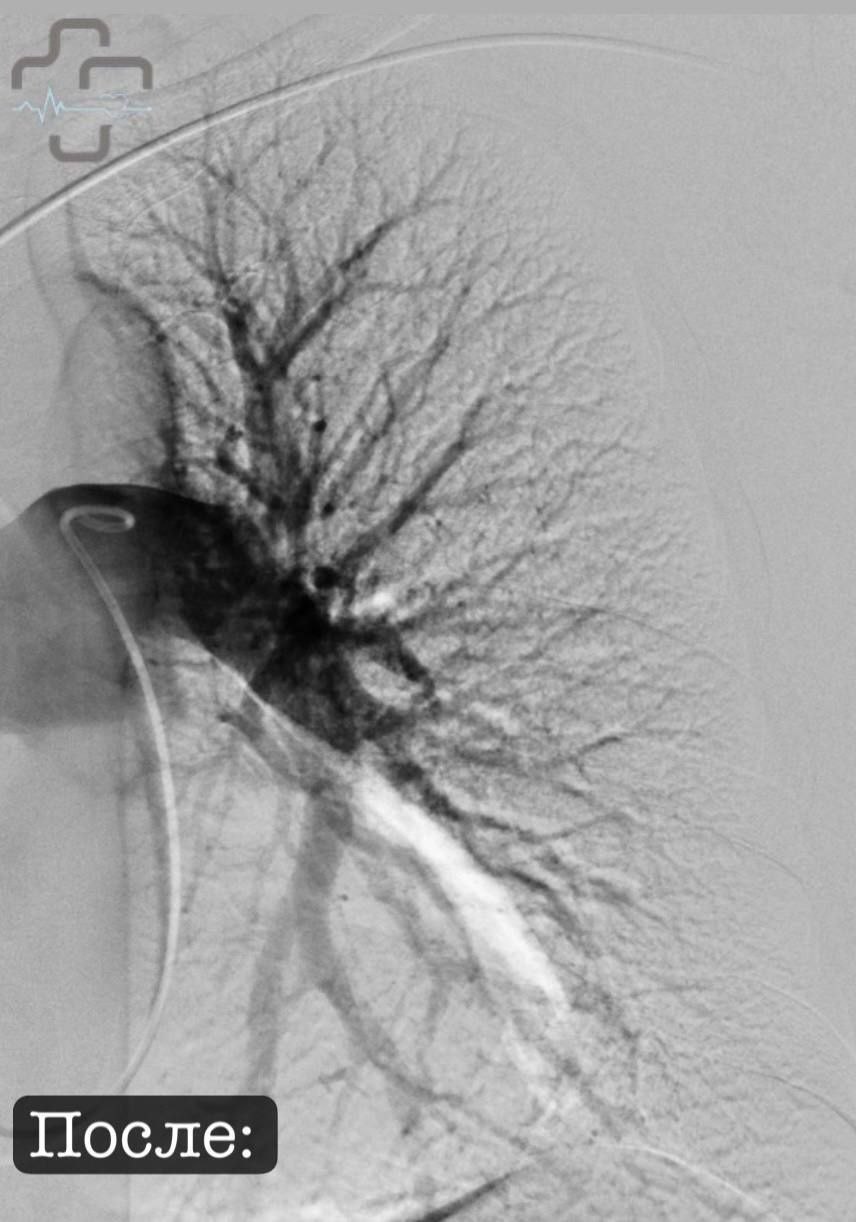

Пациентка из Оренбурга была переведена в Орск, где врачи применили ультразвуковой транскатетерный тромболизис — метод, который в России начали использовать только в 2024 году.

В отличие от обычного лечения, когда лекарство разжижают кровь во всем организме, новая методика работает точечно. Катетер вводят через бедренную вену прямо к тромбу, ультразвук помогает разрушить его и равномерно распределяет лекарство.